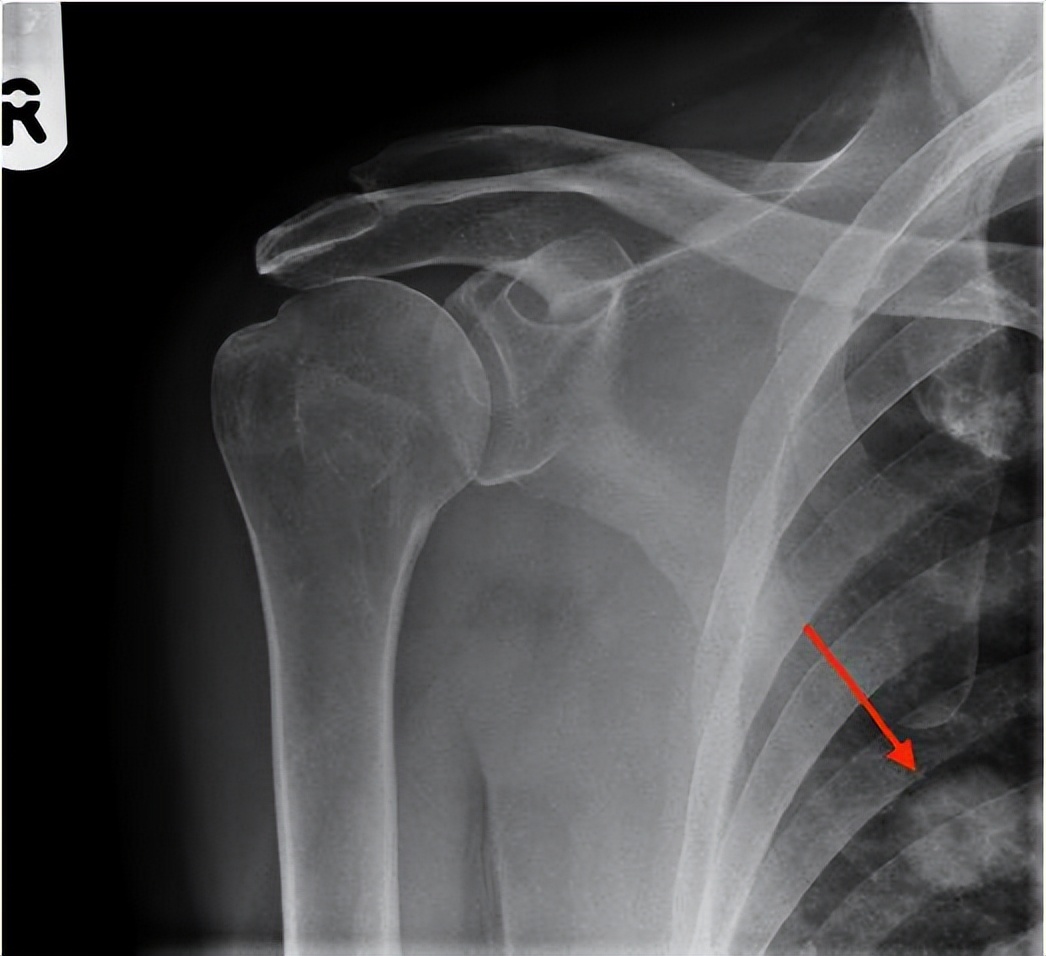

医生告诉老人:“目前来看,不排除是锁骨骨折或肩胛骨骨折的可能,需要拍一个片子。”

医生接过片子,放着阅片灯上一看,顿时眉头一皱:“老人家,骨头没什么大问题。主要的是肺部有一个阴影。”

结果发现,老人右侧肺部一个直径约2厘米的空洞性结节。经过医生的综合分析,考虑很可能是一个原发性的肺癌。

门诊医生在阅片时,细心地发现了这个不起眼的肺部阴影。